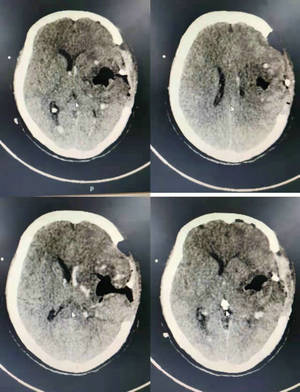

脑组织十分精细,一丝一毫的手术偏差都可能造成难以预料的后果。董伟主任凭借丰富的临床经验,在显微镜的辅助下“抽丝剥茧”,快速将出血的血管电凝止住,彻底清除出血灶,避免血肿进一步扩散。历经2小时左右,手术顺利完成。术后,患者瞳孔恢复正常,脱离生命危险。手术次日复查CT显示血肿清除彻底。目前,患者处于康复阶段。

术后次日复查CT影像